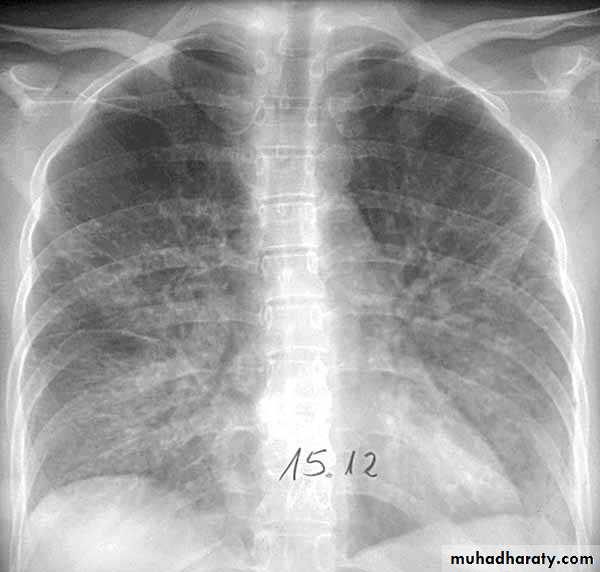

Lobar pneumonia: homogenous consolidation of one or more lung lobes, often with associated pleural effusion

A chest X-ray is usually sufficient to confirm the clinical diagnosis of pneumonia.

In lobar pneumonia, a homogenous opacity localized to the affected lobe or segment usually appears within 12 – 18 hours of the onset of illness.

Chest X-ray helps in:• Differentiating CAP from other diagnosis

• Provide information about severity (cavitation and multilobar involvement)

• Detects complications (pleural effusion or abscess formation).

• It can occasionally suggest an aetiological agent (pneumatocoele in Staphylococcus aureus pneumonia).